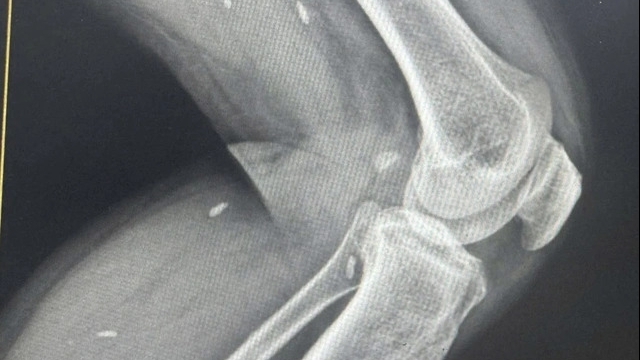

Ông Nguyễn Tuấn, Phó giám đốc Sở Y tế Hà Tĩnh lý giải xác định này dựa trên hình ảnh em bé khi ra đời. “Nhìn hình ảnh, bất cứ chuyên gia ngành sản khoa nào cũng sẽ biết ngay. Đó là một trong những căn cứ để kết luận thai lưu chết trên 7 ngày. Ngoài ra, chúng tôi còn căn cứ vào tim thai của trẻ, về tiền sử…”, ông Tuấn nói.